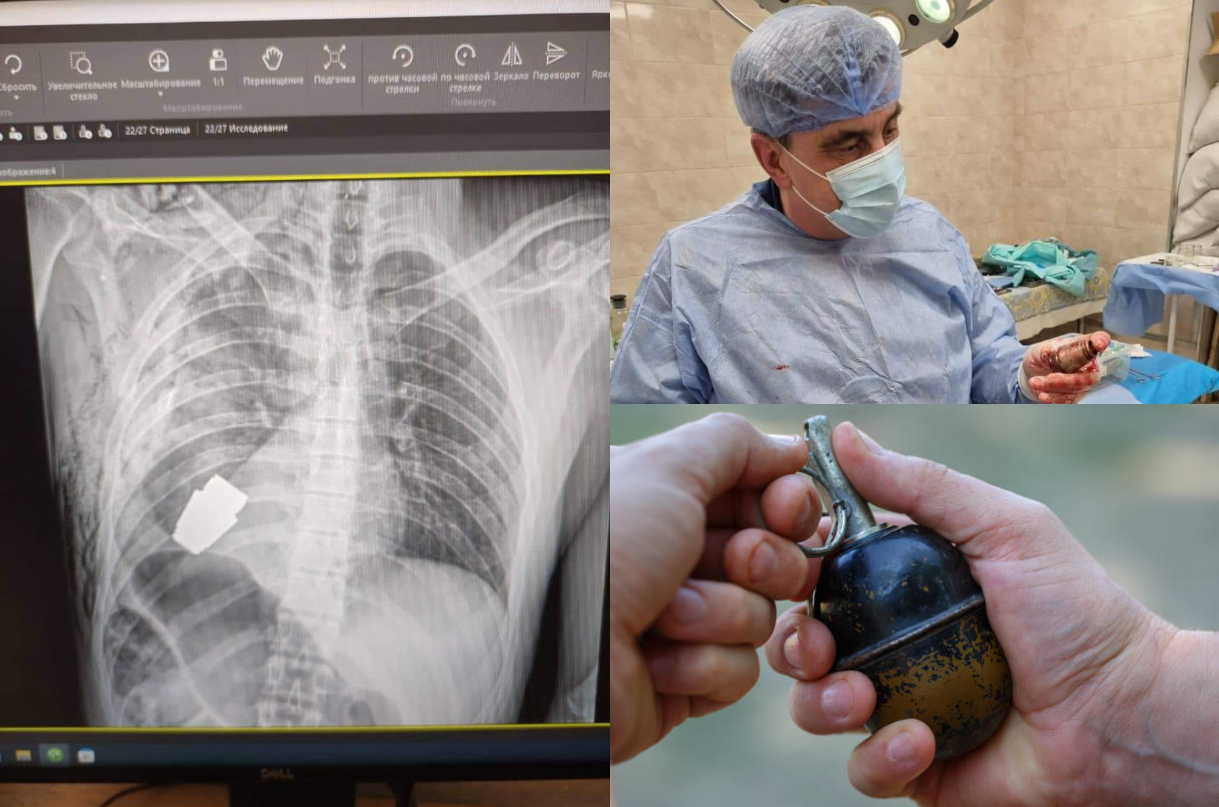

Un chirurg cu foarte mult curaj din Ucraina a reușit să salveze viața unui soldat după ce i-a scos o grenadă din corp. Aceasta era pe cale să explodeze.

Un soldat a supraviețuit în mod miraculos după ce a rămas cu o grenadă activă înfiptă în piept. Bărbatul a avut nevoie de o intervenție chirurgicală de urgență pentru a îndepărta bomba, cu toate că aceasta ar fi putut exploda în orice moment.

Armata ucraineană a adus un omagiu unuia dintre cei mai experimentați chirurgi ai săi prin intermediul unei postări pe rețelele de socializare. Este vorba despre generalul-maior Andriy Verba, cel care a efectuat operația.

Chirurgul a fost fotografiat ținând în mână bomba

Materialul exploziv este cunoscut sub numele de grenadă VOG, un proiectil conceput pentru a fi tras dintr-un lansator de grenade.

Bomba a rămas înfiptă în trunchiul unui soldat ucrainean, care a fost trimis în continuare la reabilitare și recuperare după o operație reușită.

Medicul chirurg a fost nevoit să efectueze procedura fără a utiliza electrocoagularea. Această procedură constă în folosirea unui curent electric pentru a distruge țesuturile anormale și a controla sângerarea.

Nu s-a apelat la această etodă de teamă că ar putea detona grenada.